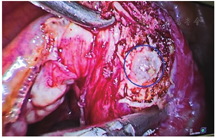

患者,41岁,因"停经37 d,左下腹痛2 d"于2018.08.24入院。末次月经2018.07.18,入院前2 d,患者出现左下腹部隐痛,无阴道出血,无肛门坠胀感,无恶心、呕吐等不适。既往生育史:1-0-1-1,2006年阴道分娩史。妇科检查:外阴已婚式;阴道畅;宫颈光,有举痛;宫体前位,饱满,压痛;左侧附件压痛,未及明显包块,右侧附件未及压痛,未及包块。2018.08.25血hCG为2 814.00 IU/L,孕酮为57.57 nmol/L。阴道B超结果提示:子宫内膜厚16 mm,左侧宫角处见混合性回声区12 mm× 9 mm×12 mm,似与宫腔相连,见血流信号,内见无回声区8 mm×4 mm×6 mm,卵黄囊似可见。2018.08.27复查血hCG为4 752.00 IU/L,孕酮为50.820 nmol/L。阴道B超结果提示:子宫内膜厚为18 mm,左侧宫角处见无回声区10 mm×9 mm×7 mm,卵黄囊可见,与内膜线不相连,左侧宫角略膨隆。于当日考虑左侧输卵管间质部妊娠,行腹腔镜下探查术,术中见子宫后位,饱满,两侧宫角处未见膨隆,双侧输卵管和卵巢未见明显异常,给予宫腔镜下检查,子宫宫腔和宫角处未见明显异常妊娠样组织。最后经阴道B超引导下切开左侧输卵管间质部,见绒毛样组织物,取出绒毛(图2),给予左侧输卵管切除术+左侧宫角部分切除修补术。术后病理:见绒毛组织。术后15 d血hCG下降至正常,恢复好。

随着B超诊断技术的不断发展,目前输卵管间质部妊娠破裂导致腹腔内大出血的概率明显降低,对于包块较小的输卵管间质部妊娠和宫角妊娠,通过经阴道彩色多普勒超声检查能较准确地做出诊断[11]。病例2,术前B超反复提示:左侧宫角或输卵管间质部妊娠可能,可术中宫腹腔镜均未见妊娠部位,最终在B超引导下精准地切开左侧输卵管间质部,找到了绒毛。蔡秋娥等报道[12]在阴道B超的引导下,见闭孔处的妊娠并取出病灶。所以术中经阴道B超的引导寻找异位妊娠部位是一个很有效的方法。